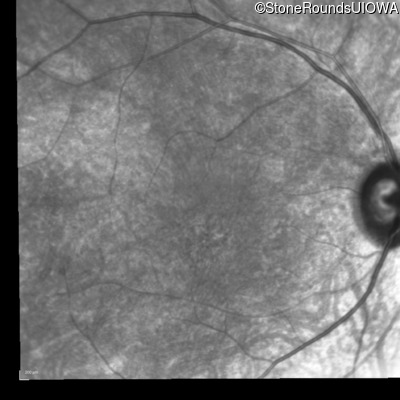

Infrared Fundus Photograph - Left - 20/100 -2 sc

Exemplar

Blue Autofluorescence - Left - 20/100 -2 sc